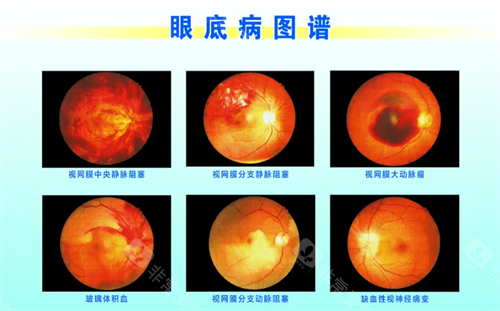

在探讨眼科疾病治疗时,眼底病的治疗备受关注,而武汉协和医院在这方面的表现值得深入了解。

很多人会问:武汉协和医院治疗眼底病好吗?下面从多个维度为大家分析。

在眼底病治疗方面,医生们能够运用可靠的技术和丰富的经验,为患者制定个性化的治疗方案。